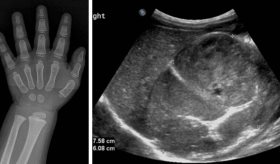

En cuanto al diagnóstico, si se sospecha un colangiocarcinoma, el médico puede realizar diversas pruebas como análisis de función hepática y del marcador tumoral CA 19-9, que pueden sugerir la presencia de cáncer.

También se emplean estudios por imágenes como ecografía, tomografía computarizada y resonancia magnética. En algunos casos se utiliza la colangiopancreatografía retrógrada endoscópica para observar directamente los conductos y tomar muestras o biopsias.